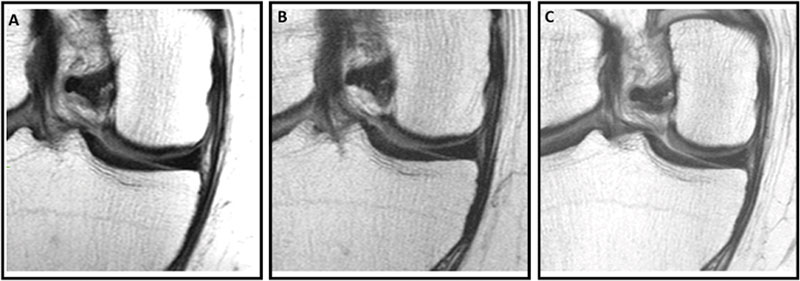

במחקר שפורסם במאי 25 בכתב העת Radiology בהובלת חוקרים מאוניברסיטת UCSF העריכו את הקשר בין זריקות תוך-מפרקיות – הליך רפואי שבו מוזרקת תרופה ישירות לחלל המפרק – לבין התקדמות דלקת מפרקים ניוונית ותוצאות קליניות לאורך תקופה של שנתיים.

נתונים נותחו ממחקר תצפיתי רב-מרכזי, אורכי, של כמעט 5,000 גברים ונשים עם דלקת מפרקים בברך – בחסות המכונים הלאומיים לבריאות – הנמצא כעת בשנת המעקב ה-14 שלו.

צוות המחקר בחן 70 משתתפים מתוכם 44 הוזרקו קורטיקוסטרואידים, ו-26 חומצה היאלורונית) אחת בברך. המשתתפים הללו עברו MRI של הברך לפני, בזמן ושנתיים לאחר ההזרקה. הם גם העריכו כמה נזק נגרם בחלקים שונים של מפרק הברך לאורך זמן באמצעות Whole-Organ Magnetic Resonance Imaging Score (WORMS). ציונים אלה הושוו לקבוצת ביקורת של 140 אנשים עם מאפיינים דומים שלא קיבלו זריקה כלשהי.

החוקרים מציינים שזהו המחקר הראשון שהשתמש ב-WORMS כדי להעריך את התקדמות דלקת מפרקים ניוונית של הברך לאחר זריקה תוך-מפרקית עם מעקב של שנתיים ושמחקרים קודמים הסתמכו בעיקר על הערכות רנטגן או MRI שדורש עיבוד מיוחד לאחר מכן. לכן שלא כמו אלה, המחקר הנוכחי השתמש בניקוד חצי-כמותי ש"ניתן לבצע בסביבות קליניות ומבודד חולים שקיבלו זריקה אחת בלבד".

המחקר מצא כי זריקת קורטיקוסטרואידים בודדת הובילה לנזק מבני גדול משמעותית במפרק הברך במשך שנתיים בהשוואה לקבוצת הביקורת ולאלו שקיבלו זריקות חומצה היאלורונית שם נצפתה הפחתה של התקדמות הנזק למפרקים ואף נראה שהאטו את הנזק בהשוואה ללפני ההזרקה. החוקרים הסבירו ש"קורטיקוסטרואידים ידועים כמפחיתים דלקת אך גם פוגעים במנגנוני התיקון של הסחוס ויכולים לעכב סינתזת מטריקס – המרכיב העיקרי של הסחוס שנותן את התכונות שלו, כמו גמישות, חוזק וכו'. לכן עם הזמן, הדבר עלול להוביל להחלשת הסחוס ולעלייה ברגישות לנזק, מה שמאיץ את התקדמות דלקת מפרקים ניוונית.

החוקרים מוסיפים ש"ישנן גם עדויות לשינויים בעצם התת-סחוסית ולסיכון לשברים מהזרקות סטרואידים".

החוקרים מקווים שמחקר זה יוביל לשימוש מושכל יותר בזריקות קורטיקוסטרואידים, במיוחד עבור חולים עם דלקת מפרקים ניוונית קלה עד בינונית שעדיין אינם מועמדים לניתוח. הם גם מציעים לבחור בזריקות חומצה היאלורונית בתדירות גבוהה יותר או לשקול אסטרטגיות חלופיות לניהול כאב שאינן מאיצות הידרדרות מבנית.